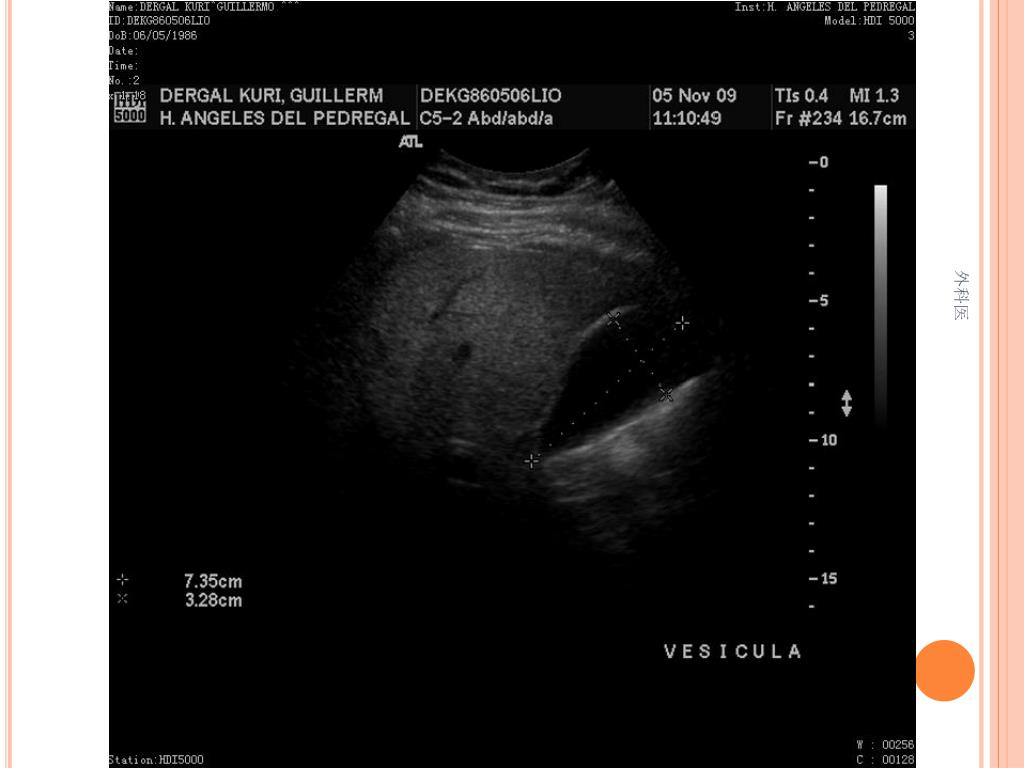

44. Tips • Leucocitos Mas de 20000/ml • Mas de 20% de la apéndices no se llenan con el bario por enema. • USG sensibilidad del 85% y Especificidad de mas 90% para Apendicitis Aguda. • TAC de Abdomen cortes de 5mm, sensibilidad y especificidad del 90% para dolor abdominal. • Analisis de 75000, taza de apendice negativa de 6% Hombres y 13% Mujeres 外科医